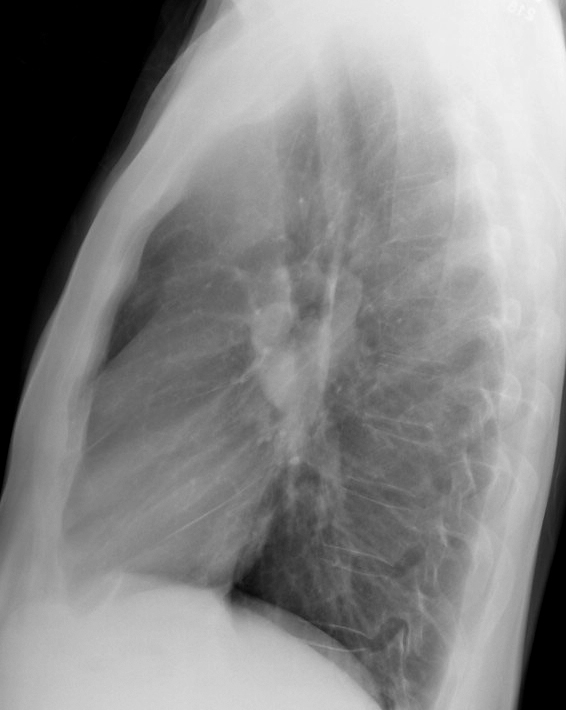

Gallery Mediastinum Lymphoma 9b

9b